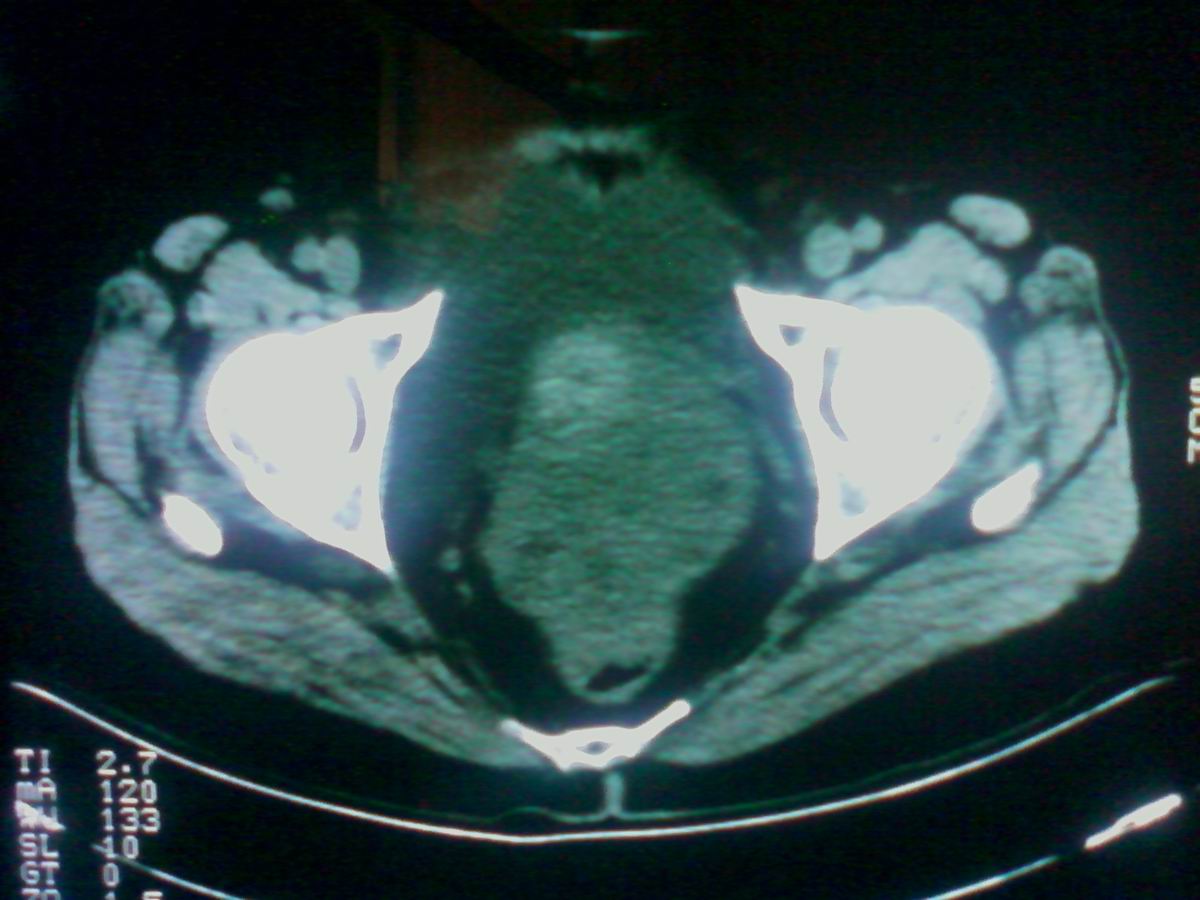

标题: CT25799:女性患者,45岁,腹胀,上腹部疼痛来诊,B超示盆腔 [打印本页]

标题: CT25799:女性患者,45岁,腹胀,上腹部疼痛来诊,B超示盆腔

考虑卵巢癌伴腹水

1)考虑卵巢恶性肿瘤。2)腹水。